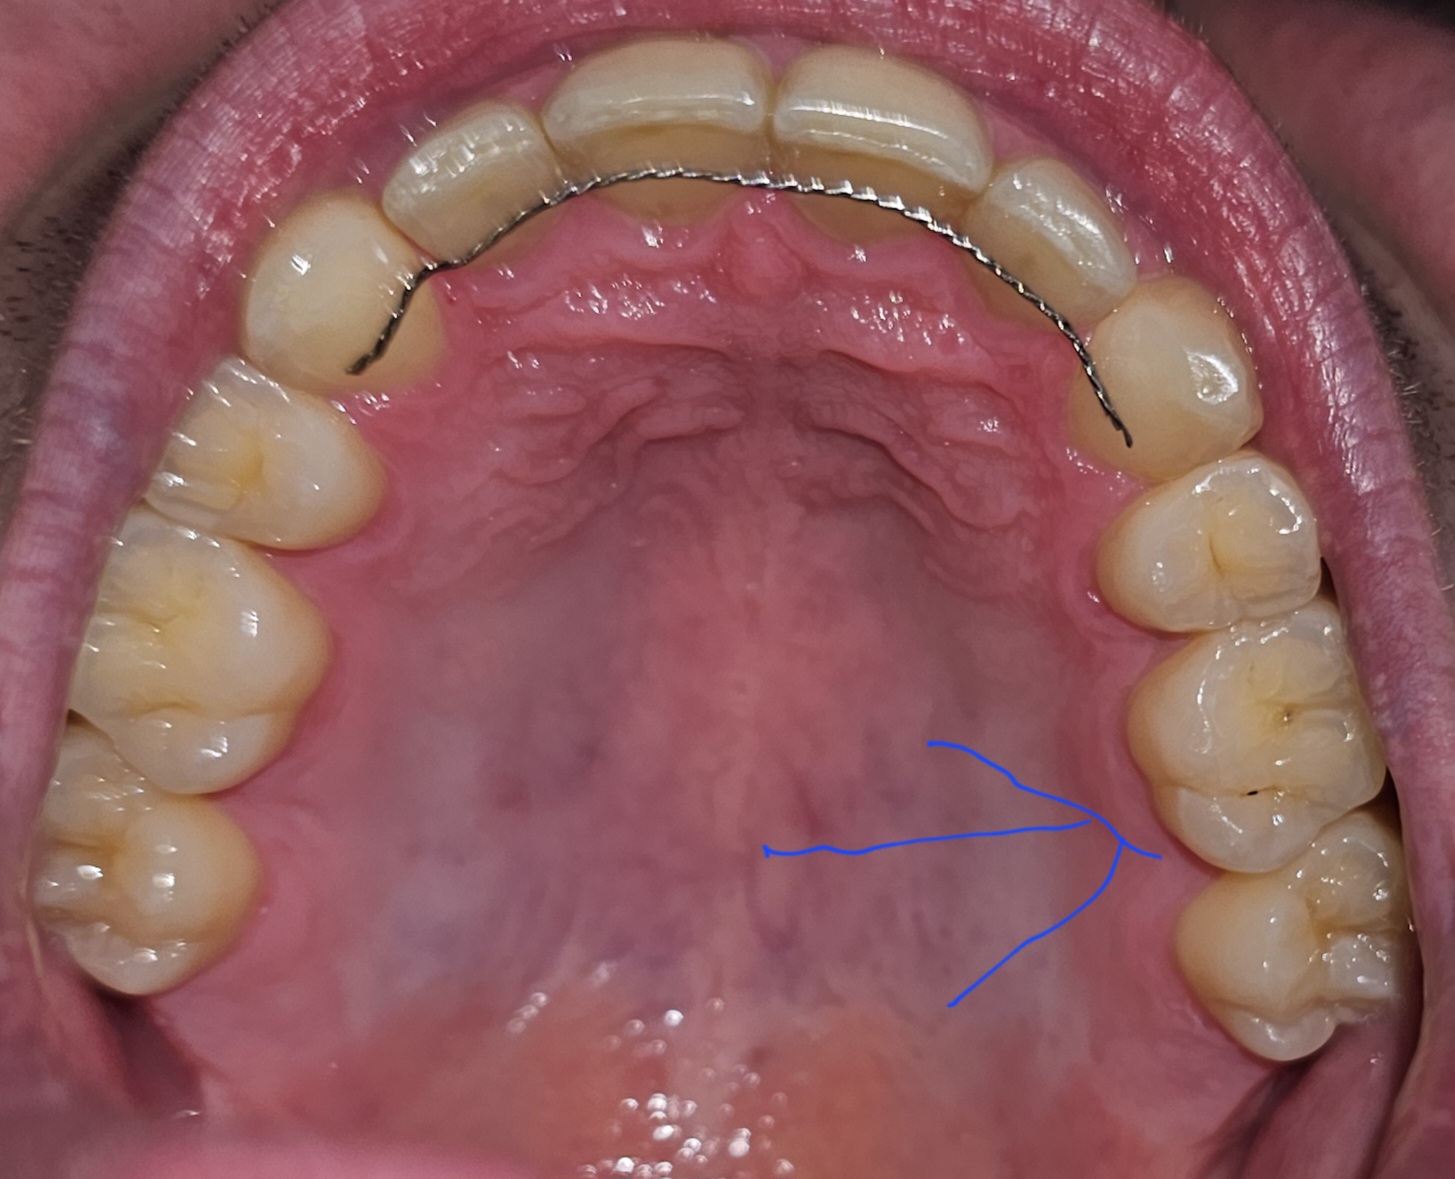

Hallo, ik ben 28 jaar en heb nog geen gaatje gehad, maar deze avond heb ik gezien dat er een zwart streepje/puntje op mijn linker kies aanwezig is, ik heb die kies extra gepoetst en het is nu veel minder zichtbaar,  maar ik vroeg me toch af of dit een gaatje of gewoon vuil is, ik heb over 3 maanden een controle bij tandarts, en wil even weten of dit zorgwekkend is en of mijn gebit er nog goed/gezond uitziet grtn